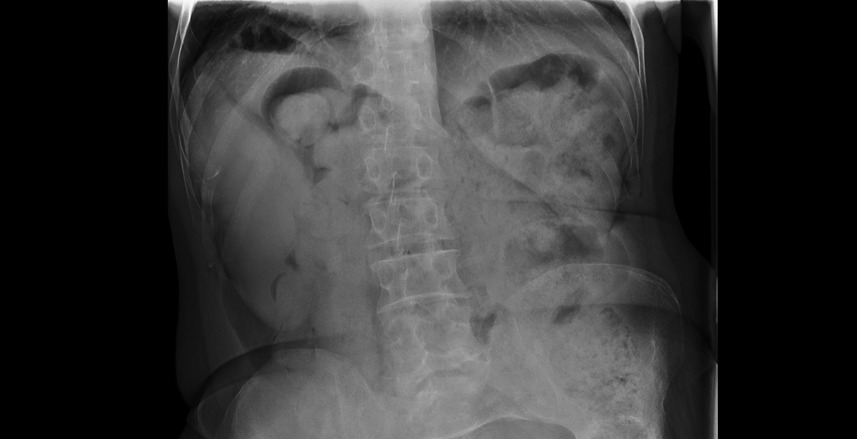

El paciente presentó mejoría rápida del dolor torácico tras analgesia, permaneciendo hemodinámicamente estable y sin nueva sintomatología. Los exámenes de laboratorio y la radiografía de tórax no mostraron alteraciones. La ecografía torácica/abdominal evidenció un situs inversus total como hallazgo incidental, sin relación con el cuadro clínico. Durante la observación evoluciona asintomático, con adecuada ventilación y sin dolor, por lo que se decide alta con educación respecto a su condición anatómica y recomendaciones para seguimiento.

La integración de un examen físico completo, en conjunto con los hallazgos característicos del electrocardiograma y la confirmación estructural mediante ecocardiograma, permite establecer con precisión el diagnóstico de situs inversus. El examen físico orienta desde los primeros momentos al identificar la posición anómala de los ruidos cardíacos y, el electrocardiograma aporta patrones eléctricos sugestivos de inversión anatómica. Finalmente, el ecocardiograma y Rx confirman la disposición especular de las estructuras torácicas y cardíacas.